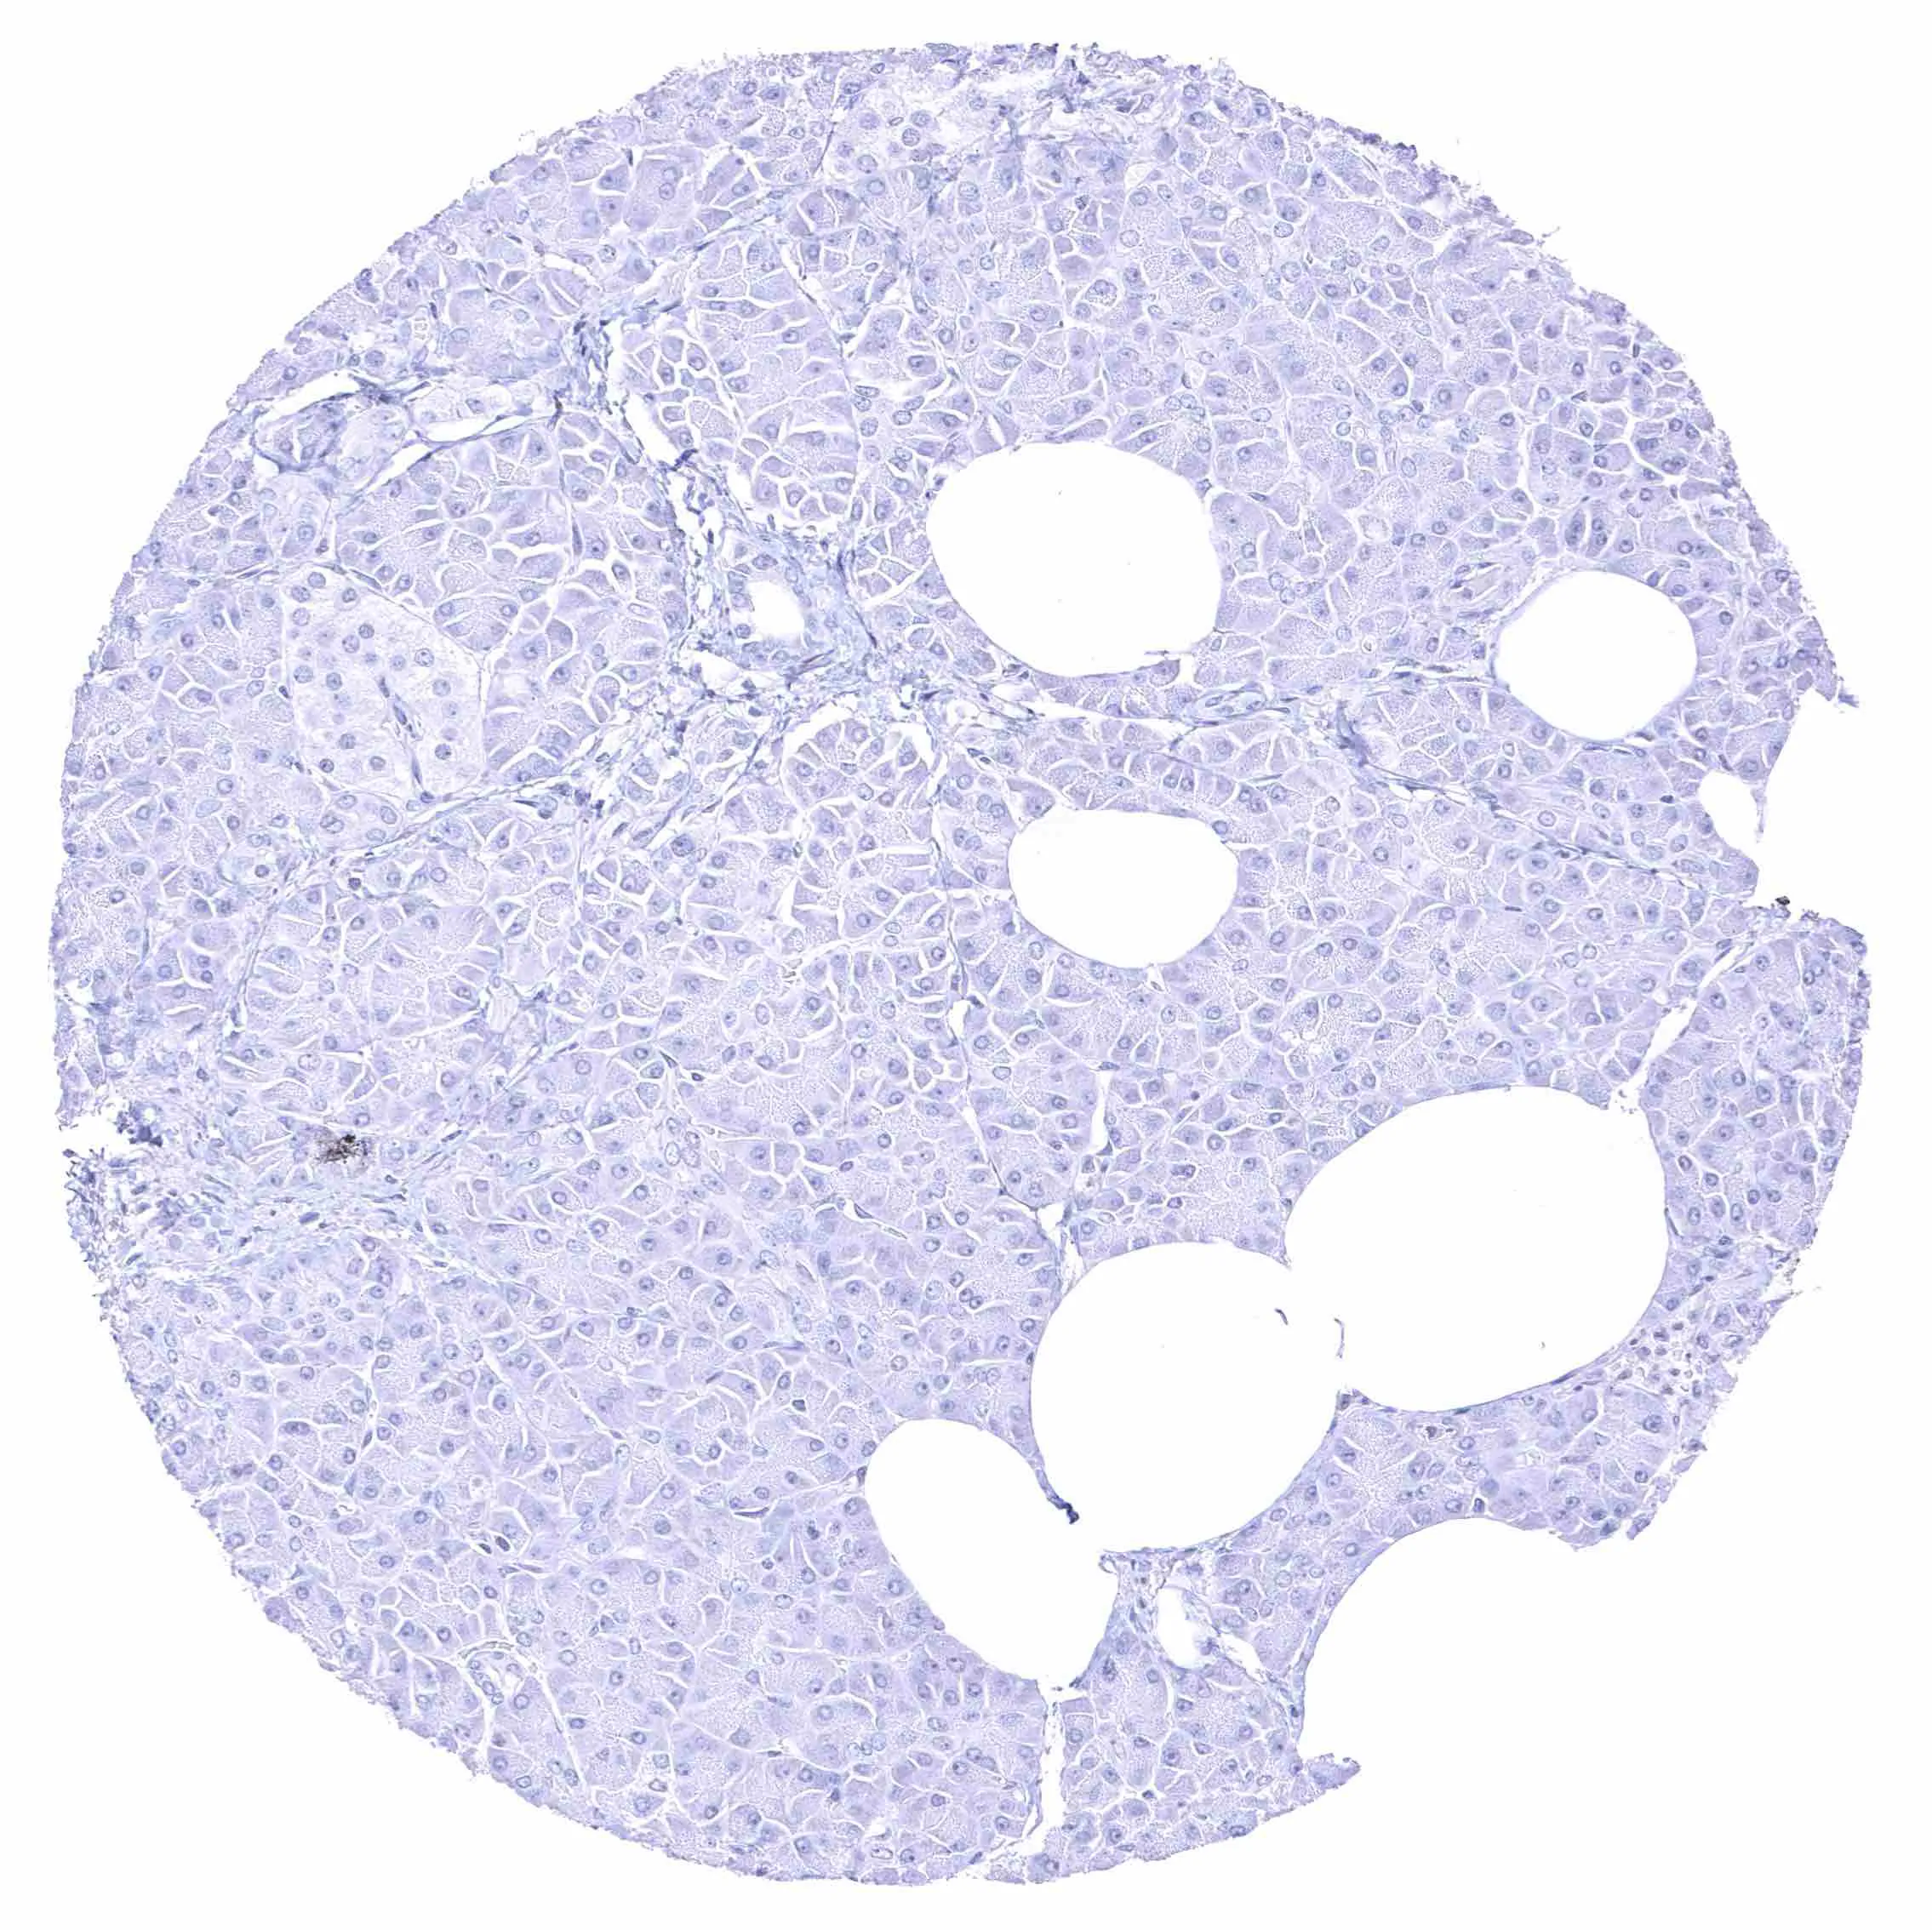

Kidney, cortex – Distinct membranous NPR-C staining at the luminal cell border of a subset of tubuli, the parietal membrane of the Bowman capsule, and in glomerular endothelial cells.

Kidney, cortex – Distinct membranous NPR-C staining at the luminal cell border of a subset of tubuli, the parietal layer of the Bowman capsule, and in glomerular endothelial cells.